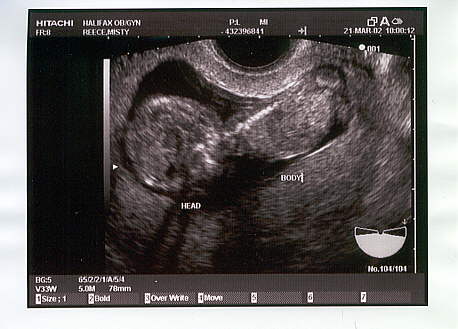

This was our first look at 12 weeks.